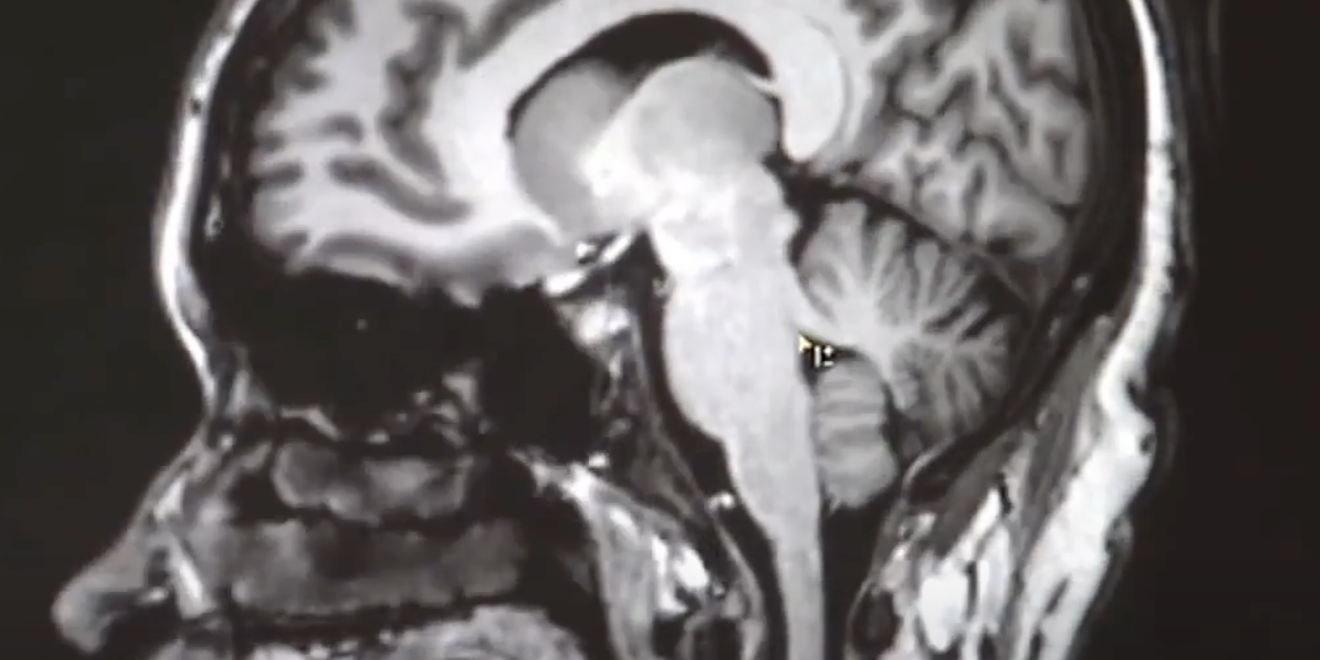

The Department of Neurology has a strong commitment to and already considerable history of, excellent and ground breaking clinical and translational research in the neurosciences.

The faculty are actively engaged in basic, translational and clinical research in various neurological diseases including amyotrophic lateral sclerosis, Alzheimer’s disease, frontotemporal dementia, gene therapy in neurodegenerative disease, multiple sclerosis, ischemic hemorrhagic stroke and traumatic brain injury among others